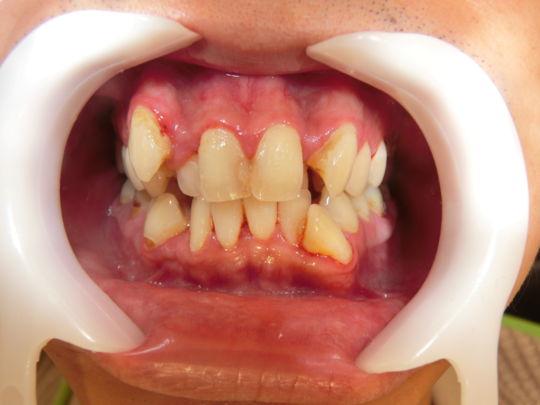

治療前

治療説明 歯科矯正でも目立ちにくい矯正方法であるマウスピース矯正で治療しました

治療期間 2年

治療費用498000 円